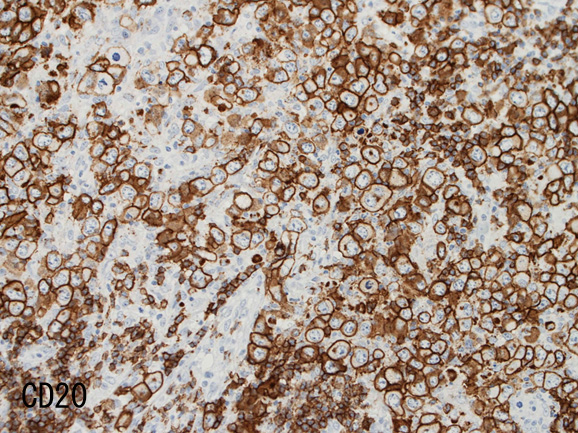

免疫染色

- RS細胞様巨細胞, LCLの大型細胞は B細胞マーカ(CD20, CD79a)が陽性。いずれかが消失することもある。通常腫瘍細胞の50%以上が陽性となりHodgkin病との鑑別点となる。

免疫染色†

腫瘍細胞はCD20+, CD30+, CD15-, PAX-5+, Oct.2+, BOB.1+(Oct2, BOB1は田丸先生の染色結果), EBER-ISH+, EBNA2-

| CD20 | PAX-5 | CD30 | EBER-ISH+ |